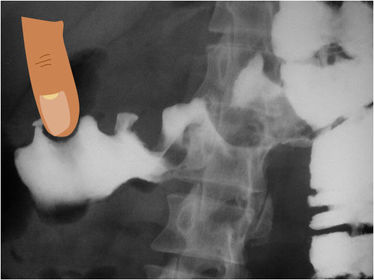

Es el signo radiográfico de colitis isquemica Signo de la huella digital

Signo radiográfico de cáncer de colon Signo de la manzana mordida